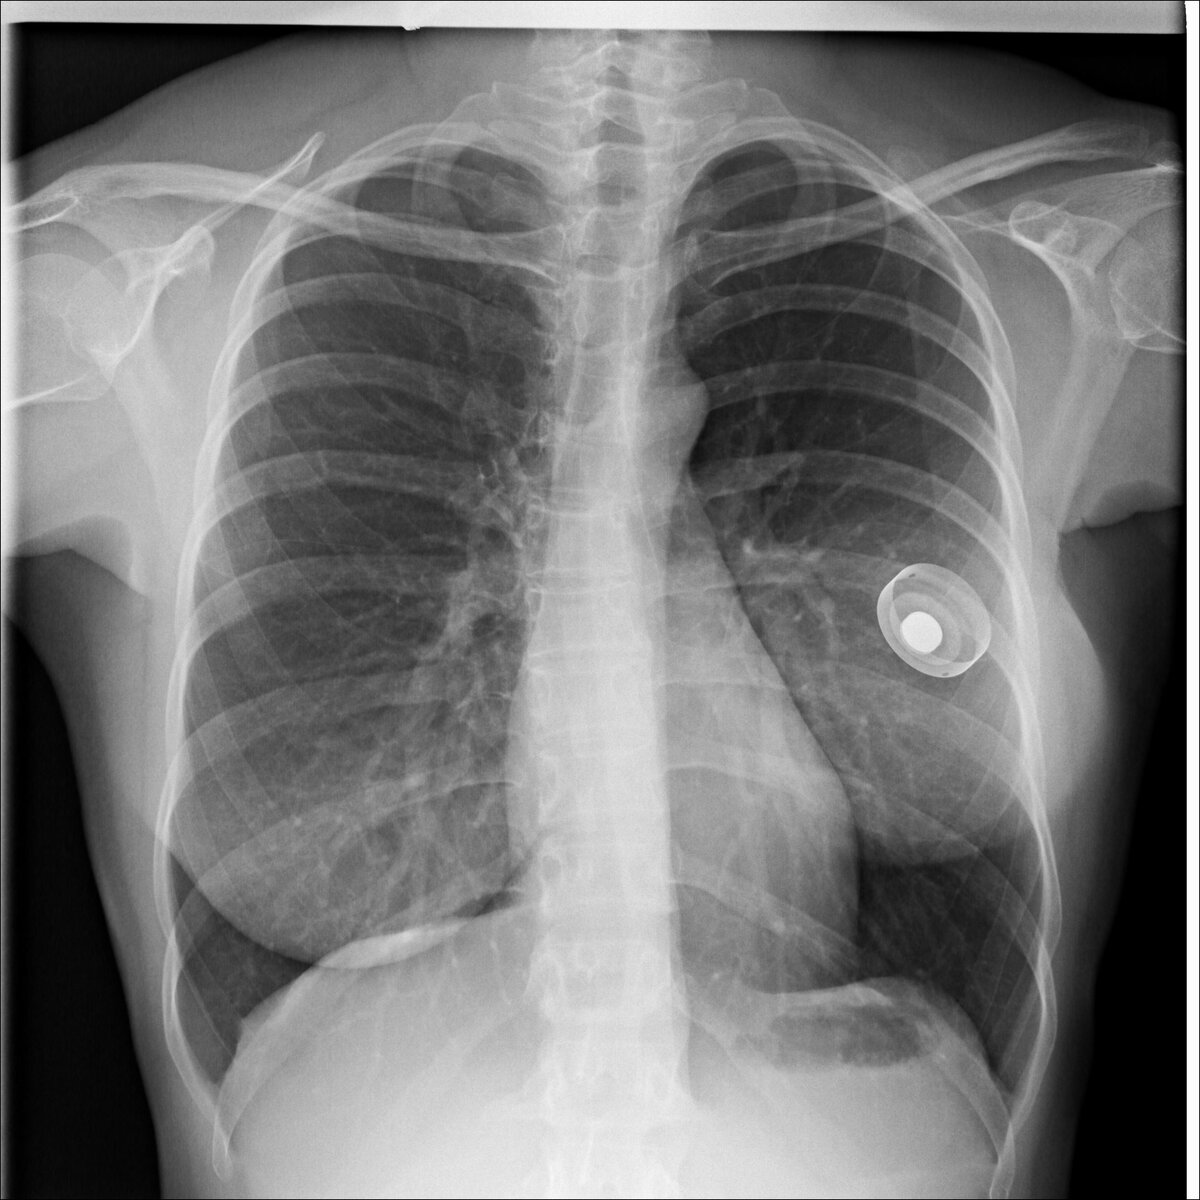

In the photo of the lungs on the left, in the area of the mammary gland, a foreign object is subcutaneously located. By density it is close to a tree or plastic. The shape is rounded. Obviously the subject is made by man

На снимке легких слева в районе молочной железы подкожно располагается инородный предмет. По плотности он близок к дереву или пластику. Форма округлая. Явно предмет сделан человеком.

These are the so-called PowerPorts for the introduction of drugs into the patient.

Это так называемые порты для введения лекарственных средств в организм пациента.

A young doctor or medical student may be confused by this shadow. But there is nothing wrong with it. PowerPorts are used when the patient is on an outpatient basis (they are not kept permanently at the hospital), but this necessitates the constant administration of drugs intravenously.

Молодого врача или студента медика может смутить данная тень. Но ничего страшного в ней нет. PowerPorts используются тогда, когда больной находится на амбулаторном лечении (ненаходится постоянно в стациаонаре), но при этом возникает необходимость постоянного введения лекарственных средств внутривенно.

Most often, such devices are used in the treatment of cancer and the patient undergoing chemotherapy.

Чаще всего такие устройства используются при лечении рака и прохождении пациентом химиотерапии.

PowerPort is installed under the skin and injected into one of the vessels. Most often in the subclavian vein.

Устанавливается PowerPort под кожу и вводится в один из сосудов. Чаще всего в подключичную вену.